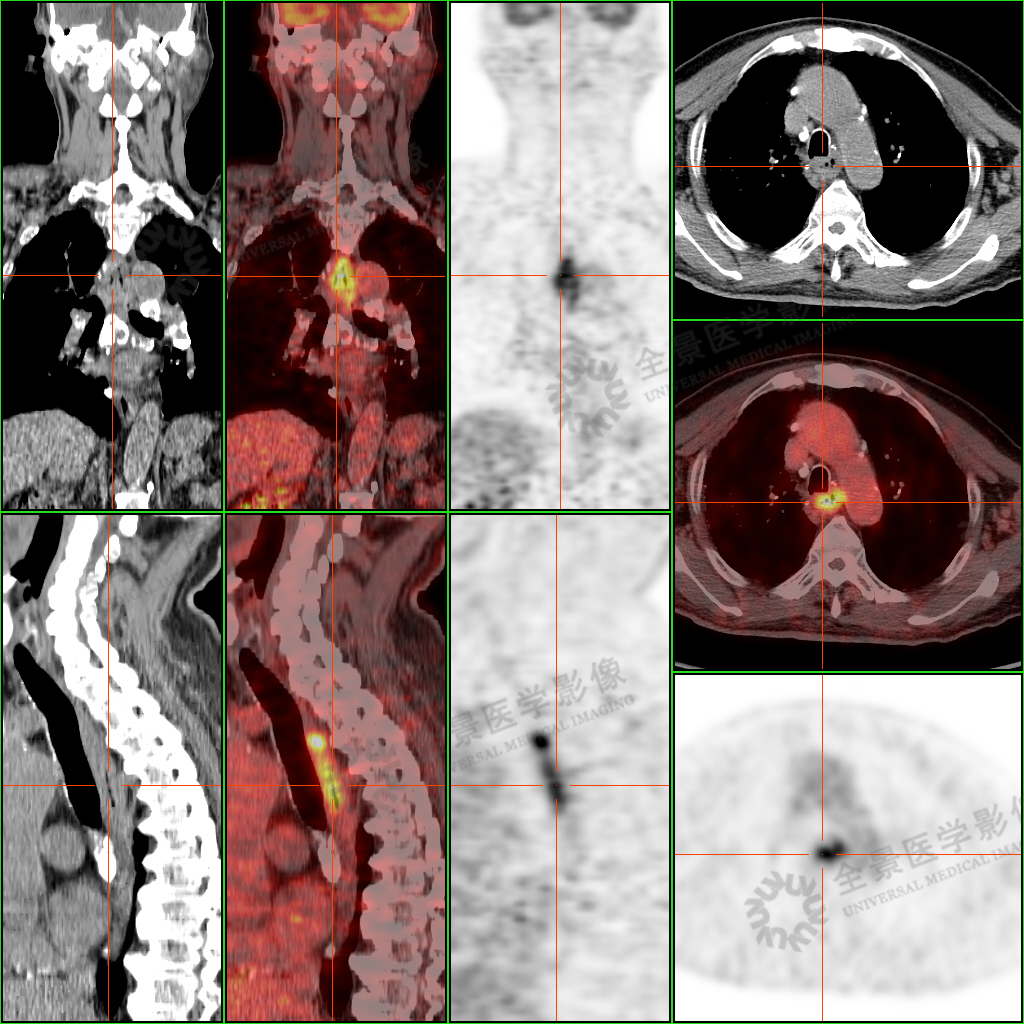

PET/CT 检查图像:

PET/CT 检查显示: 陈老师食管胸中段壁增厚、毛糙,FDG 摄取增高,考虑食管癌可能,建议进一步通过胃镜活检明确诊断。